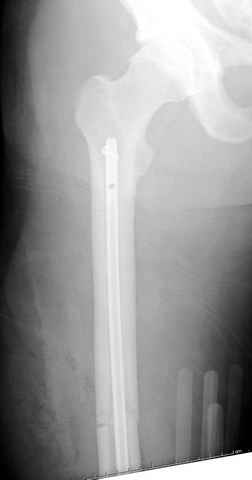

По поводу открытого перелома больной ургентно взят на ретроградное интрамедулярное штифтование, после рутинного дебрайдмента и фасциотомии на бедре и на голени.

постоперационные